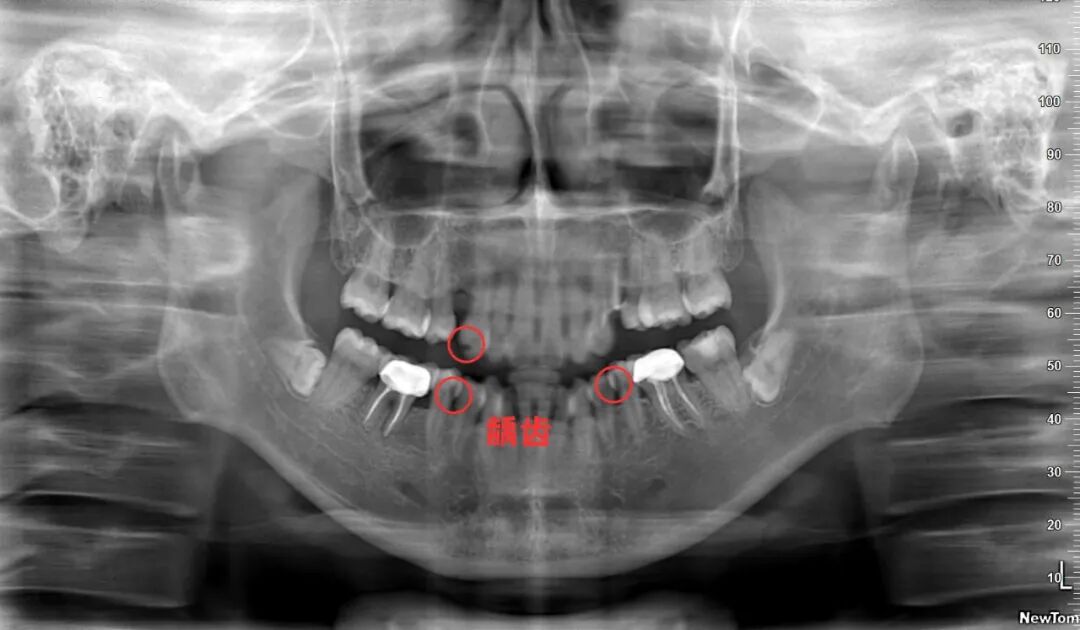

常见的蛀牙通常可以通过牙片发现,尤其是龋坏比较多的,在牙片上会出现黑色阴影的缺损。但如果是邻面龋,就需要到口腔机构,让医师用探针、口镜等进行检查确定。